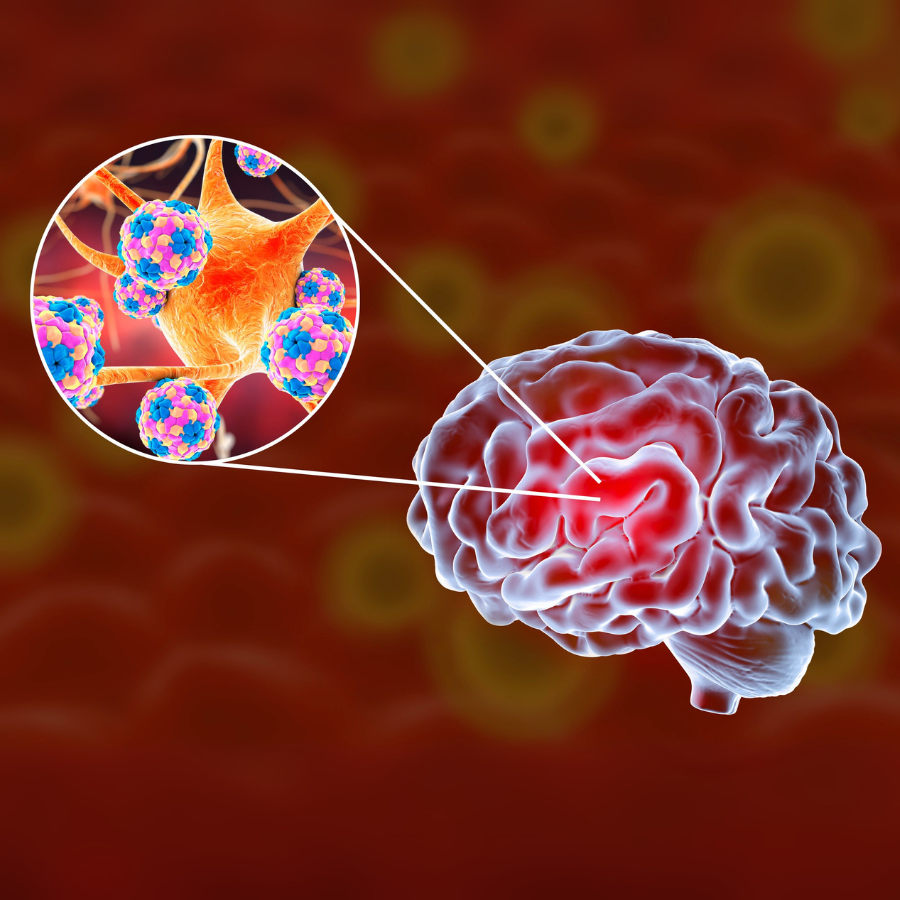

Encephalitis is inflammation of the brain tissue, usually caused by a viral infection. It can lead to fever, headache, confusion, seizures, or changes in consciousness. Early recognition and treatment are vital to protect brain function and reduce risks.